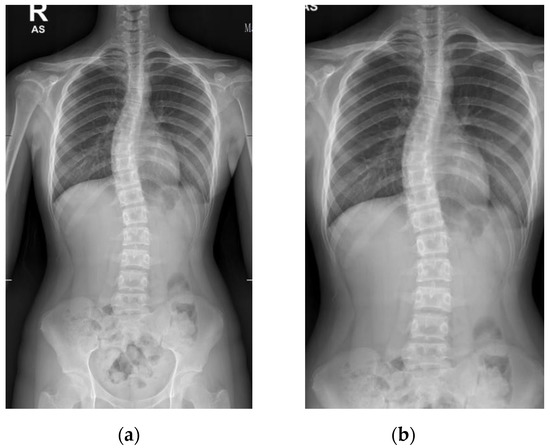

The Cobb angle measurement of the scoliotic spine is prone to inter- and intra-observer variations in the clinical setting. This paper proposes a deep learning architecture for detecting spine vertebrae from X-ray images to evaluate the Cobb angle automatically. The public AASCE MICCAI 2019 anterior-posterior X-ray image dataset and local images were used to train and test the proposed convolutional neural network architecture. Sixty-eight landmark features of the spine were detected from the input image to obtain seventeen vertebrae on the spine. The vertebrae locations obtained were processed to automatically measure the Cobb angle. The proposed method can measure the Cobb angle with accuracies up to 93.6% and has excellent reliability compared to clinicians’ measurement (intraclass correlation coefficient > 0.95). The proposed deep learning architecture may be used as a tool to augment Cobb angle measurement in X-ray images of patients with adolescent idiopathic scoliosis in a real-world clinical setting. Full article

Show Figures

Figure 1